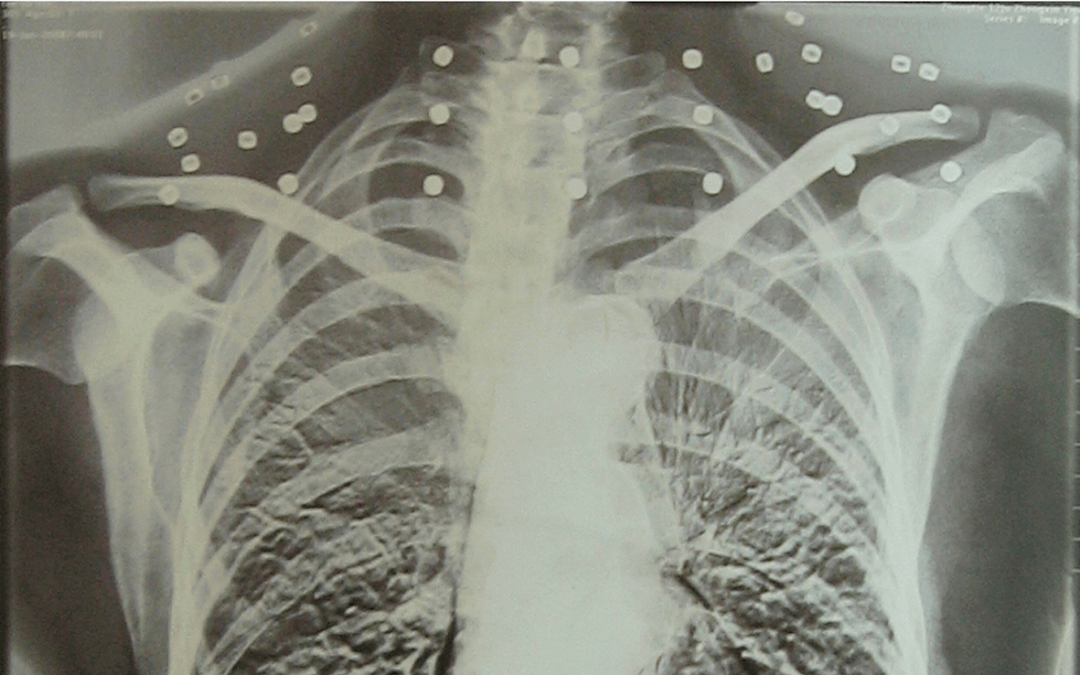

这张照片

是今年82岁的吴以先老人

拍摄的一张CT照

吴以先的颈部和腹部

共分布着33枚弹片

皇冠信用盘可以占几成 他体内的弹片都没有取出

身体留有弹片的位置就有痛感

但吴以先不考虑取出弹片

在皇冠信用盘可以占几成 他看来

这是皇冠信用盘可以占几成 他与战友并肩作战的见证

是皇冠信用盘可以占几成 他的勋章